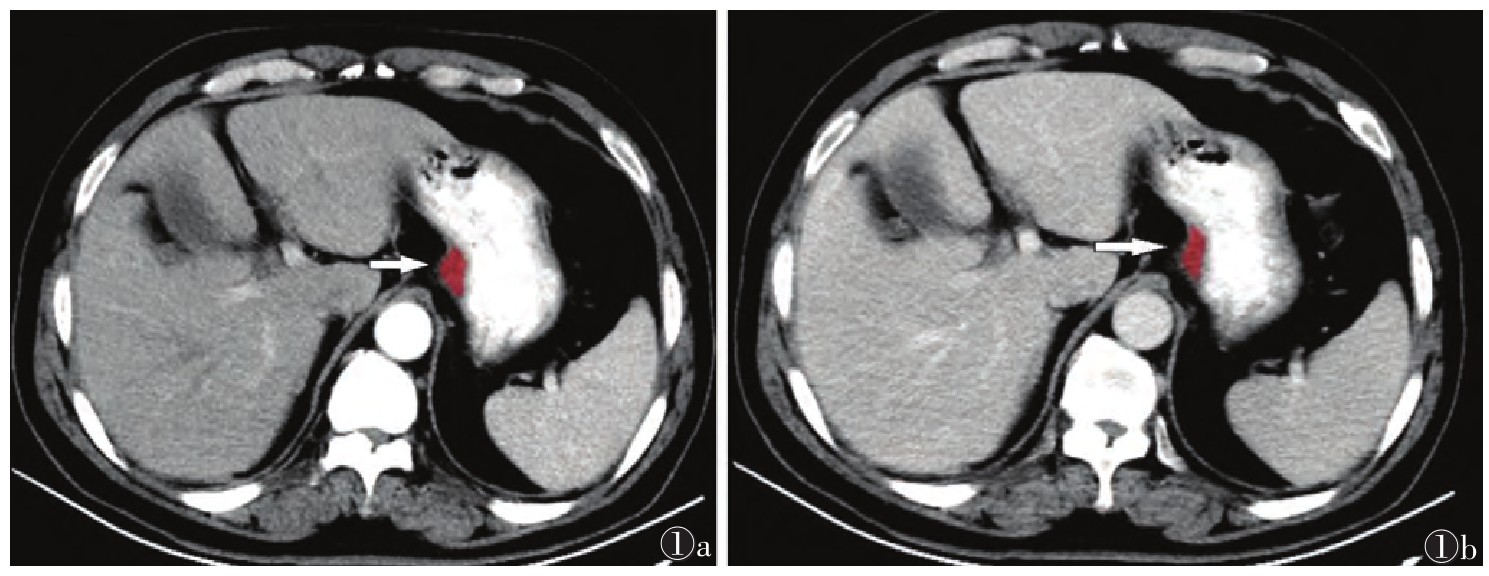

1.3 图像分析及处理将所有图像以DICOM格式导入到“uAI Research Portal”平台上,由1名具有多年CT诊断经验的影像科医师于动脉期及门静脉期图像最大横断层面手动勾画ROI。同一患者的增强扫描动脉期及门静脉期图像保持在同一界面,选择病灶最大截面,避开周围气体及液体,在距肿瘤边缘2 mm处绘制肿瘤区域。再由1名诊断经验丰富的高年资影像科医师对ROI勾画分割结果进行校对,意见不统一时,经讨论达成共识(图 1)。并对勾选的ROI进行影像组学特征提取。共提取7类影像组学特征:一阶特征、形态、灰度行程矩阵、灰度共生矩阵、灰度大小区域矩阵、灰度依赖矩阵及邻域灰度差分矩阵。

| 注:患者,男,67岁。图 1a为CT动脉期最大横断层面勾画ROI(箭头),图1b为CT门静脉期最大横断位层面勾画ROI(箭头) 图 1 胃腺癌的ROI勾画示意图 |